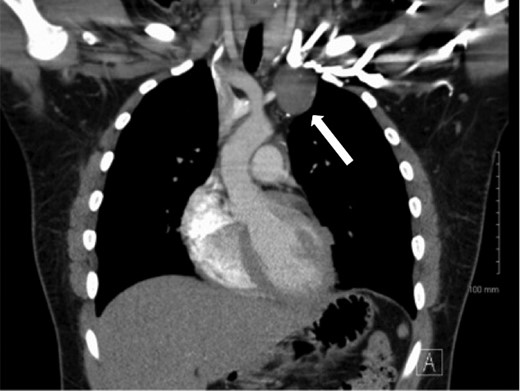

A 17-year-old male presented with complaints of left-arm swelling and occasional pain. Imaging obtained of the chest and neck revealed a large anterior mediastinal mass involving the major venous structures of the left chest (Fig. 1). Computed tomography (CT)-guided needle biopsy was performed, with inconclusive results, and this was followed by a left video-assisted thoracoscopic surgery (VATS) procedure yielding enough tissue for formal diagnosis of an epithelioid hemangioendothelioma. After extensive multidisciplinary consultation and preoperative planning, the patient was taken to the operating room for a median sternotomy, thymectomy and en-bloc excision of the tumor and vessels (Fig. 2). Vascular reconstruction of the left brachiocephalic and left subclavian vein was performed with an 8 mm ringed polytetrafluoroethylene graft, with an additional end-to-side anastomosis of the left internal jugular vein to the graft. The patient tolerated the initial procedure well, was extubated on postoperative Day 1 and advanced to an oral diet. After several days, large-volume milky drainage from the chest tube was evaluated and presence of a chyle leak confirmed. The patient returned to the operating room on postoperative Day 6 for a right VATS with ligation of the thoracic duct. Final tumor measurements were 7.5 × 5.5 × 3.5 cm, and final pathology confirmed an epithelioid hemangioendothelioma with no mitoses, <5% necrosis and a final pathologic staging of pT2b. The patient has since recovered uneventfully and was discharged home in stable condition.

Computed tomography demonstrating a mass in the left chest involving the brachiocephalic vein.